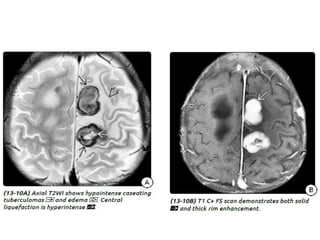

Tuberculous meningitis • Tuberculousmeningitis is the most common presentation of intracranial tuberculosis, and usually refers to infection of the leptomeninges. • Tuberculous meningitis, although seen in all age groups, has a peak incidence in childhood (particularly 0-4 years of age) in high prevalence areas.

Tuberculous meningitis

• Tuberculous meningitis is the most common presentation

of intracranial tuberculosis, and usually refers to infection of

the leptomeninges.

• Tuberculous meningitis, although seen in all age groups, has a

peak incidence in childhood (particularly 0-4 years of age) in

high prevalence areas.